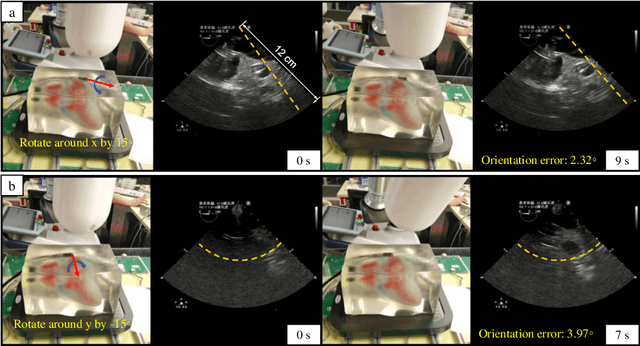

Abstract:This paper presents a closed-loop magnetic manipulation framework for robotic transesophageal echocardiography (TEE) acquisitions. Different from previous work on intracorporeal robotic ultrasound acquisitions that focus on continuum robot control, we first investigate the use of magnetic control methods for more direct, intuitive, and accurate manipulation of the distal tip of the probe. We modify a standard TEE probe by attaching a permanent magnet and an inertial measurement unit sensor to the probe tip and replacing the flexible gastroscope with a soft tether containing only wires for transmitting ultrasound signals, and show that 6-DOF localization and 5-DOF closed-loop control of the probe can be achieved with an external permanent magnet based on the fusion of internal inertial measurement and external magnetic field sensing data. The proposed method does not require complex structures or motions of the actuator and the probe compared with existing magnetic manipulation methods. We have conducted extensive experiments to validate the effectiveness of the framework in terms of localization accuracy, update rate, workspace size, and tracking accuracy. In addition, our results obtained on a realistic cardiac tissue-mimicking phantom show that the proposed framework is applicable in real conditions and can generally meet the requirements for tele-operated TEE acquisitions.